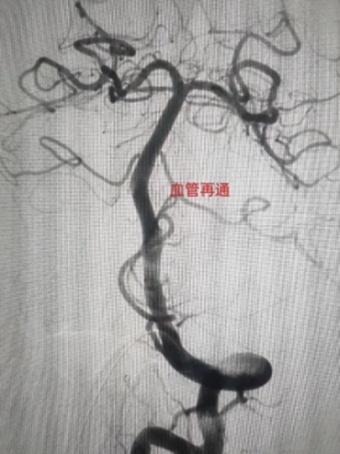

6月7日下午,家住长竹园乡的刘先生突然出现左侧肢体无力,双眼向右侧斜视(凝视),言语不清、口角歪斜等症状,下午3点家属将其送入我院,急诊行头颅CT未见出血,但其右侧颈内动脉末端及大脑中动脉可见高密度征,考虑为大血管病变所致的急性脑梗死,NIHSS评分:14分,mRS评分4分,因无溶栓禁忌,与家属沟通后给予急诊静脉溶栓(阿替普酶,0.9mg/Kg体重)治疗。溶栓大约10分钟左右患者开始出现烦躁,头痛,(NIHSS评分:14分,mRS评分5分)急诊头颅CT未见出血转化,在右侧大脑中动脉供血区出现大片状低密度灶,情况变得更加凶险,卒中团队综合考量认为患者此时急需血管开通治疗以避免脑细胞进一步坏死,再次与患者家属沟通病情后开始急诊取栓治疗。下午3点30分患者被紧急推入介入手术室。

在卒中中心团队的默契配合下,手术顺利取出血栓,实现左侧大脑中动脉完全再通。从动脉穿刺成功到血管完全再通历时仅40分钟。术后患者生命体征平稳,术后1周,患者病情稳定,神志清楚,对话流利,凝视症状缓解,NIHSS评分由14分变为8分。